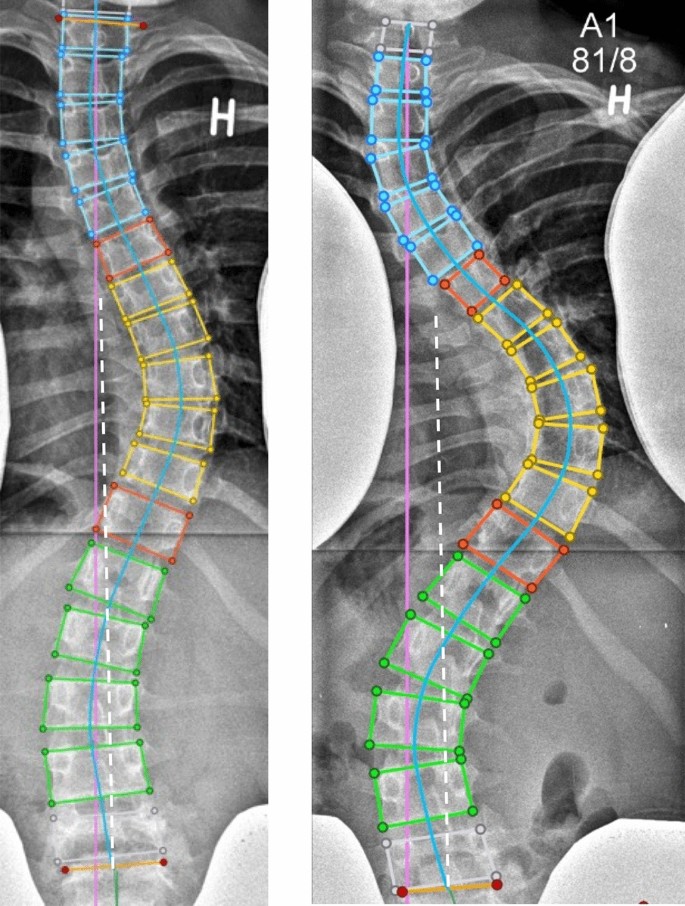

اعوجاج العمود الفقري هو انحناء جانبي غير طبيعي للعمود الفقري، قد يكون مصحوبًا بدرجة من دوران الفقرات. يظهر غالبًا خلال مرحلة الطفولة والمراهقة، خاصة أثناء النمو السريع. يمكن أن يكون الاعوجاج:

الاعوجاج حالة مستمرة ولهذا السب قد تحتاج تدخلًا في مراحل مختلفة من العمر. وبفضل وجود تقنيات التصنيف المعتمدة ، يمكن للأطباء تصميم خطة علاجية مخصصة تضمن تدخلاً جراحيًا عند الضرورة أو العلاج غير الجراحي قبل ذلك، لتفادي الاضطراب في الوظائف التنفسية أو أي أعراض متأخرة. فريقنا المحترف يضم نخبة من الأطباء والمتخصصين الذين يجمعون بين الخبرة والاحترافية لتقديم خطة علاجية غيرر جراحيه شاملة ومخصصة لحالتك، تضمن السيطرة على الانحناء ومنع زيادته.